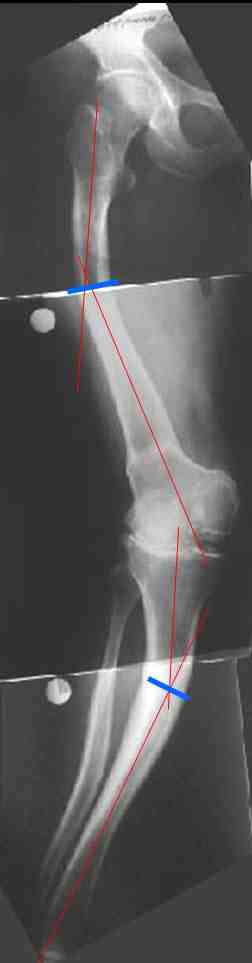

Обратилась дама 57 лет с намерением протезировать коленный сустав. Имется грубая осевая деформация (см. рентгенограммы). Встает вопрос насчет улучшения оси конечности. Даже с мобилизацией на пртяжении при таком вальгусе малоберцовому нерву может не поздоровиться. Уважаемые коллеги, как лучше провести коррекцию? Какой сегмент, на каком уровне, на какую величину? Что бы Вы исправили до протезирования, что можно оставить и сделать вместе с замещением сустава?

В данном случае перед эндопротезированием мы бы корригировали оси бедренной и большеберцовой костей (см. вложение). Дистальный эпидиафизарный угол бедра будет корригирован при эндопротезировании. Тип остеотомии и коррекции деформации (клиновидная резекция - одномоментная коррекция; формироване треугольных или трапециевидных регенератов во времени) - исходя из

относительной длины конечности.

На бедре дистальный отдел в сгибательной установке после, видимо, когда-то сделанной корригирующей остеотомии. Не надо ли на том же уровне все-таки "разогнуть" бедро до протезирования? Сам протез, наверно, можно поставить в большем или меньшем "сгибании", но весь дистальный эпиметафиз бедра и все нижележащее оказывается кзади от механической оси бедра. Насколько это допустимо, не ведет ли к расшатыванию протеза? Или можно как-то рассчитать такой наклон протеза, что он компенсирует это смещение?

И нет ли смысла аппаратом исправить не только кривые диафизы, но и взимоотношения собственно суставных концов бедренной и большеберцовой костей, они ведь там контактируют с вальгусом градусов 25? Это позволит дозированно удлинить мягкие ткани по латеральной стороне.

Это один из самых сложных вариантов для эндопротезирования, т.к. мы имеем деформацию бедренной кости в трех проекция, думаю, что есть и

ротационная деформация, плюс к этому - деформация голени. Однозначно в таких случаях, в отличии от возможностей при эндопротезировании ТБС необходимо выполнить корригирующие остетомии на двух уровнях. Что касается сгибательно установки мыщелков бедра - думаю, что это не является проблемой, особенно если на операции будет испрользован заднестабилизированный протез. Относительно вальгуса - все не так однозначно - возможно, что деформация слегка преувеличена за счет проекционной установки из-за ротационной деформации. Поэтому планирование операции необходимо будет делать только после коррекции деформации.